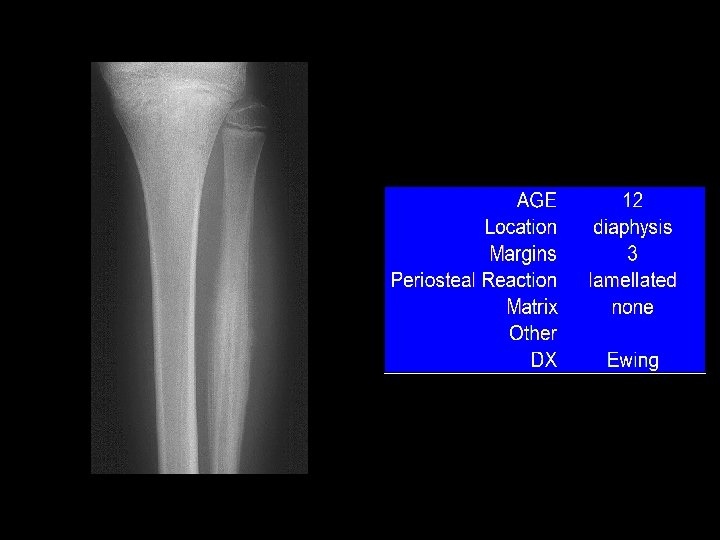

Example 9

Example 9 “onion-skin”

Example 9

Example 9 “onion-skin”